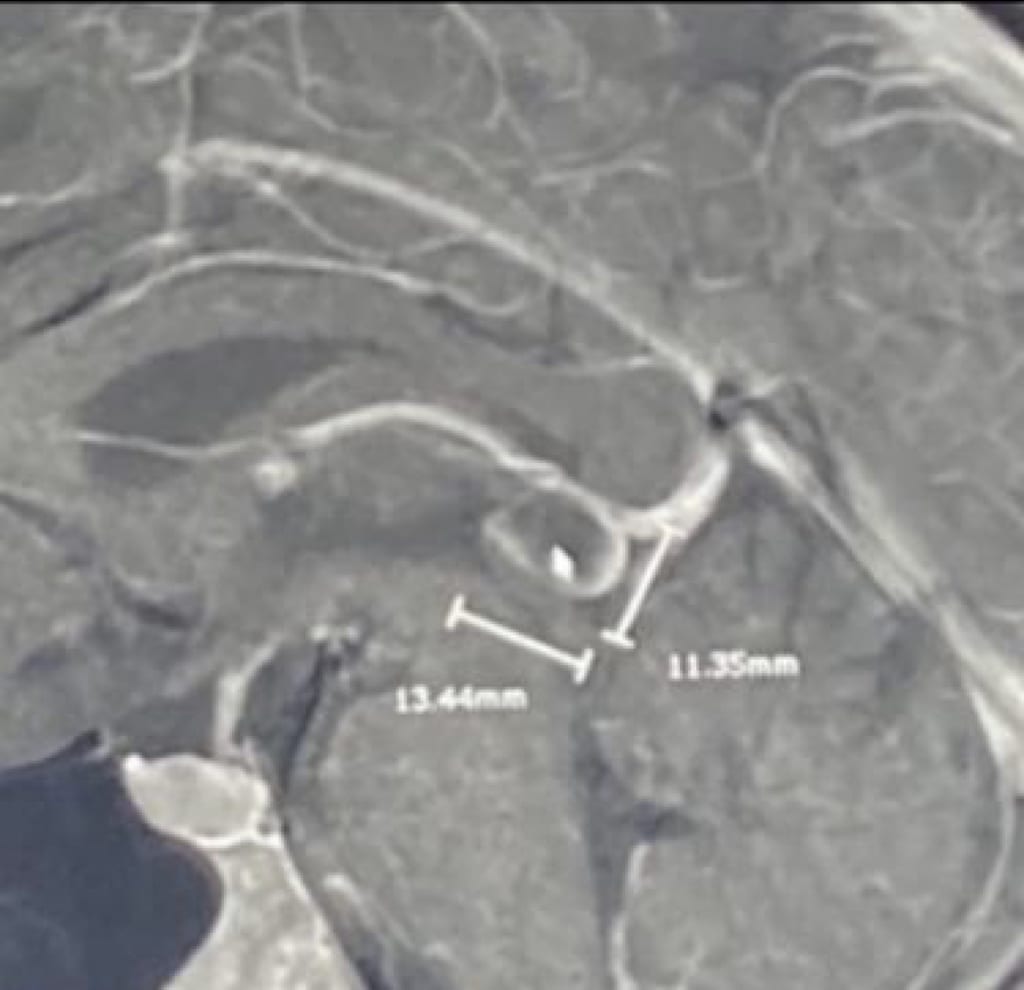

Almost a decade later, I am in the hospital again due to a number of complications, one of them being extreme dehydration. My brain felt like it was on fire and I thought surely it was my time to go. However, after several rounds of saline and an MRI, they found something in my brain: a 1.36 cm calcified pineal gland tumor. Guess it was in my head after all. From being diagnosed with anxiety and several other mental illnesses, it felt like all the answers to most of my problems were located on the jarring image of my brain scan and the abnormal growth within.